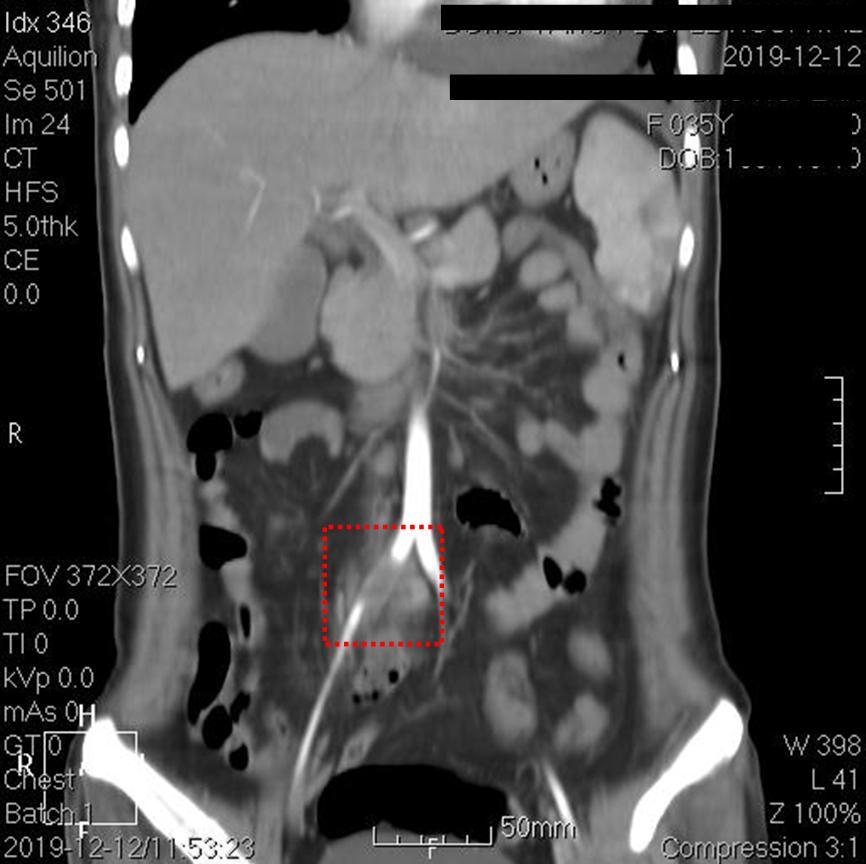

上图红框内为右髂总动脉,可见一段长约2.5厘米的管腔闭塞。